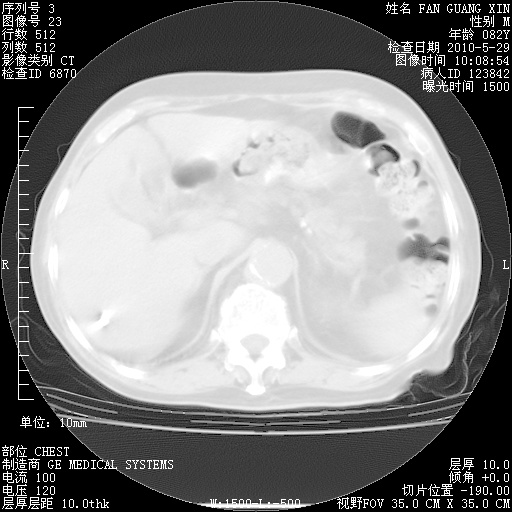

治疗3周后的肺部CT纵隔窗

再治疗10天后的肺部CT

再治疗10天后的肺部CT 纵膈窗

阅读此次胸部CT,肺间质渗出性改变较入院时有吸收。目前从体温、白细胞、中性分叶明显增高,肯定存在细菌感染(发生医院感染哦,若无消化道及泌尿系统等感染的依据,肺部感染可能大)。若你院头孢哌酮舒巴坦钠耐药率较高,同意你的方案,若48小时体温仍高,可考虑使用碳青霉稀类抗菌药物,同时可予超声雾化、注意滴数时加大液体量。白蛋白33.30g/L较低哦,需加强营养等支持治疗。